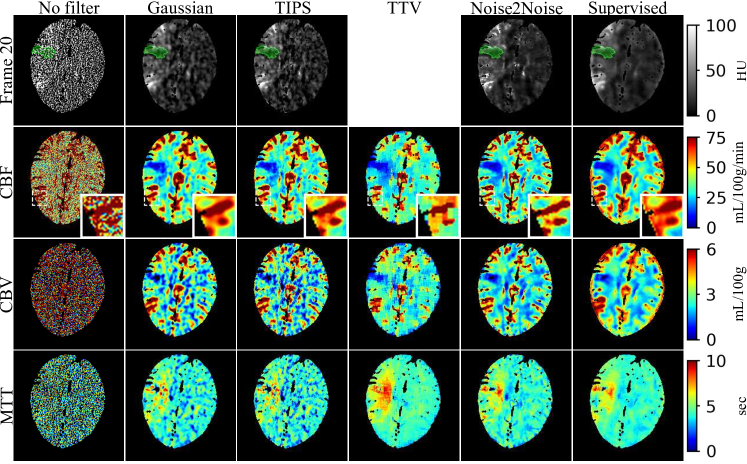

Refer to caption

Figure 3: Denoising results of all the algorithms for one of the testing simulation slices under N0=2×105subscript𝑁02superscript105N_{0}=2\times 10^{5}. The concentration maps at the 20th frame (near the peak of AIF), CBF, CBV and MTT are given. The time-concentration map is not given for TTV since TTV does not denoise the time frame images.

The denoising results for one of the testing slices under N0=2×105subscript𝑁02superscript105N_{0}=2\times 10^{5} are given in figure 3. The parametric maps were almost unreadable if no filter was applied to the CTP images. Both Noise2Noise and supervised learning achieved significantly reduced noise in the time-frame, CBF, CBV, and MTT images, where the gain was the most significant in CBV and MTT images. In the CBF images, the small penumbra area pointed by the black arrows were severely distorted in the Gaussian, TIPS and TTV results, but were much better restored in the Noise2Noise and supervised learning results. Noise2Noise had similar CBF and CBV images compared to supervised learning, but it had slightly noisier MTT images due to the noise amplification of the dividing.